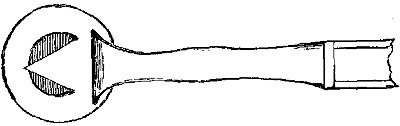

2. Ligature of Lingual.—To secure this vessel either before it becomes concealed by the hyo-glossus, or after it is under the muscle, a curved incision is necessary, following the line of the hyoid bone, and especially of its greater cornu, but a line or two above its upper border. After the skin and platysma are divided, the posterior belly of the digastric must be{33} recognised, which again will guide to the posterior edge of the hyo-glossus. The edge of the sub-maxillary gland may very probably require to be raised out of the way. The artery can then be secured, either before it dips under the hyo-glossus muscle, or after it has done so, by the division of a few of its fibres on a director. Care is needed to avoid injury of the hypo-glossal nerve, which lies above the muscle.